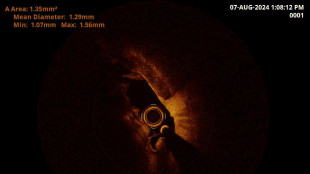

Aneurisma aortico addominale operato grazie a angiografo smart

A Busto Arsizio la prima struttura pubblica con sala 'ibrida'